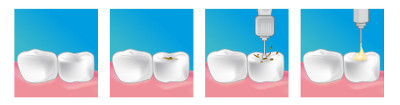

Le traitement vise à arrêter l'évolution de la carie et à éliminer les zones tissulaires abimées, favoriser la cicatrisation des tissus sains sous-jacent, éviter la récidive, restaurer la forme anatomique et fonctionnelle de la dent. Ainsi, lorsque les caries ne sont pas trop profondes, on réalise des soins conservateurs. Le praticien procède à l'éviction du tissu carié, souvent sous anesthésie locale, puis, en fonction de la profondeur de la carie et de la position de la dent, met en place un amalgame ou un composite.

Composites

Ce type de matériau permet des obturations esthétiques grâce à sa capacité de prendre la couleur de la dent qui l'entoure. La variété de la palette des couleurs est telle que le praticien peut se rapprocher au plus près de la couleur naturelle de la dent. Il existe des composites classiques en mélange de deux composants et des composites photopolymérisables qui durcissent très rapidement en présence d'un puissant rayon lumineux bleu. Ces matériaux sont particulièrement esthétiques.

Inlays Onlays

Les inlays, onlays sont des reconstitutions prothétiques par incrustation de matériau coulé au laboratoire. Lorsque la dent cariée a été particulièrement endommagée, on envisage les inlays, ou incrustation C’est un bloc, en général en céramique (de la couleur des dents) scellé à l'aide d'un ciment dans une cavité aux parois de laquelle il s'adapte en reproduisant l'anatomie occlusale de la dent et ses rapports avec les dents voisines. Cette reconstitution permet de traiter les dommages causés par la carie et de maintenir votre dent vivante.